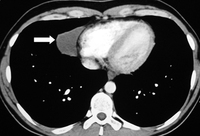

Imagem por tomografia computadorizada (TC) de grande carcinoma tímico (seta branca) com invasão esternal (seta amarela)

Dos acervos do Dr. Mario Gasparri e do Dr. Nicholas Choong

Veja esta imagem em contexto nas seguintes seções: